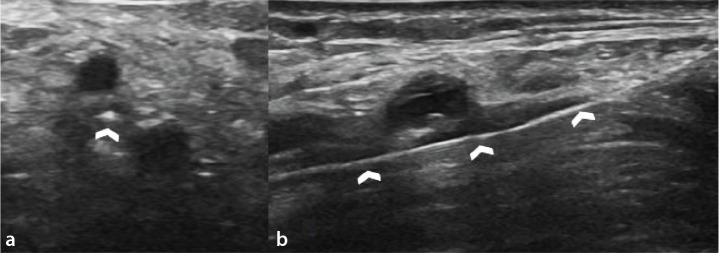

Purpose: Peripheral arterial disease (PAD) is increasingly prevalent, particularly among the aging population. Retrograde tibiopedal access (RTPA) has emerged as a useful endovascular treatment for PAD. However, there is limited research examining factors that influence the efficacy of RTPA. To investigate factors affecting the access, crossing, and recanalization success rates of RTPA for infrapopliteal PAD treatment.

Methods: A retrospective study was conducted on 720 patients who underwent endovascular treatment for PAD. Of these, 104 patients (mean age: 65.5 ± 16.2; 89 men) with 131 RTPA trials were included in the final evaluation. The disease and its duration, Rutherford score, smoking status, access site, and its occlusion status, access, crossing, and recanalization success were noted. Data were analyzed using Pearson's chi-square and Mann-Whitney U tests and multivariate logistic regression to evaluate the impact of various factors on success rates.

Results: The access success rate was 82.6%, the crossing success rate was 95.4%, and the recanalization success rate was 74%. Access success was significantly higher when the dorsal pedal artery (DPA) was the access artery compared with the posterior tibial artery (91.3% vs. 74.2%, P = 0.009). Access success was notably lower in patients with thromboangiitis obliterans compared with patients with diabetes mellitus (DM) and non-DM atherosclerosis (68.6% vs. 90.3% and 80.3%, P = 0.019). Recanalization success was higher when the puncture site was non-occluded (76.7% vs. 53.5%, P = 0.023).

Conclusion: The study suggests that RTPA is a generally effective and safe technique for infrapopliteal PAD treatment. The most favorable outcomes are observed in individuals with DM who have a non-occluded DPA at the puncture site. Recanalization success is only affected by the patency of the artery at the puncture site.